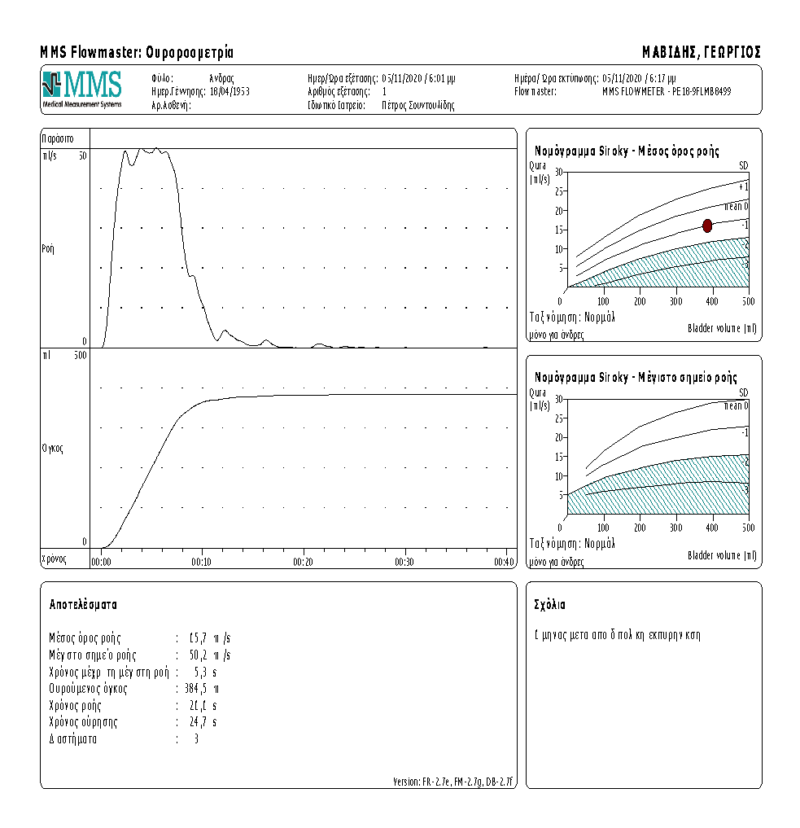

Ο μέσος χρόνος χειρουργείου είναι 90 λεπτά και κατά μέσο όρο αφαιρείται πάνω από το 70% του συνολικού όγκου του προστάτη. Ο καθετήρας αφαιρείται το επόμενο πρωί της επέμβασης ή ακόμη κα την ίδια ημέρα. Η απώλεια αίματος είναι ελάχιστη (μέση πτώση της αιμοσφαιρίνης ήταν -1.04 g/dl), ενώ κανείς ασθενής δεν έχει χρειαστεί μετάγγιση. Οι ασθενείς επανελέγχονται σε 6 εβδομάδες όπου διαπιστώνεται σημαντική βελτίωση στα συμπτώματα (IPSS), στην ροή των ούρων (Qmax), στον όγκο ούρησης και στο PSA. Πιο συγκεκριμένα, μετεγχειρητικά η μέση μείωσή του IPSS (δείκτης βαρύτητας συμπτωμάτων) σε σύγκριση με την προεγχειρητική τιμή ήταν 12,42 μονάδες. Αντίστοιχα, η μέση αύξησή τουQmax (δείκτης ροής ούρων) σε σύγκριση με την προεγχειρητική τιμή ήταν 10,38 ml/sec. Ο όγκος ούρησης μετά την επέμβαση εκπυρήνισης προστάτη αυξήθηκε κατά 90 ml σε σύγκριση με πριν την επέμβαση. To PSA μειώθηκε κατά 2,14 ng/ml μετά την επέμβαση με μέση μείωση της τάξης του 70%. (εικόνες 11-12)

Εικόνα 12. Ουροροομετρία μετά από εκπυρήνιση προστάτη